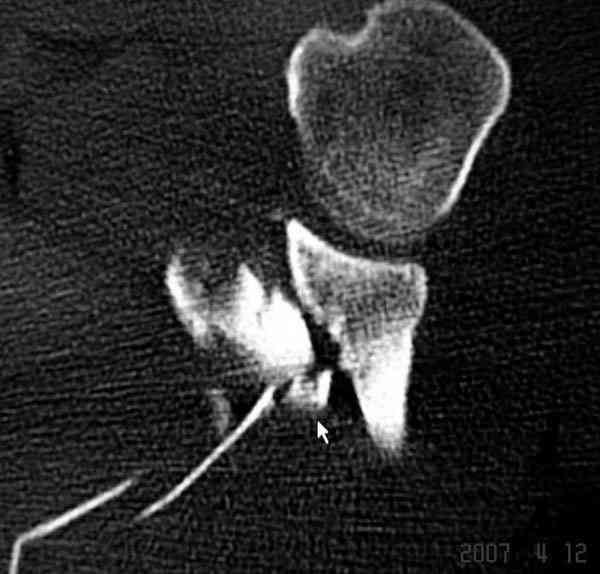

На снимке (№6 компьютерная томограмма и 3D №7) перелом клювовидного отростка.

Передним дельтопекторальным Bankart доступом намного легче провести фиксация отростка, но тогда репозиция и фиксация колонн затрудняется, поэтому был применен стандартный Judet задний доступ.

Репозицию смогли сделать пальцами через щель между

шейкой и телом лопатки (последний 3D снимок)

Двумя шурупами сзади на пластине (вместе шайбы)

провели удержание репозиции, а фиксацию провели

следующим косым шурупом.

Последующие этапы на снимках.